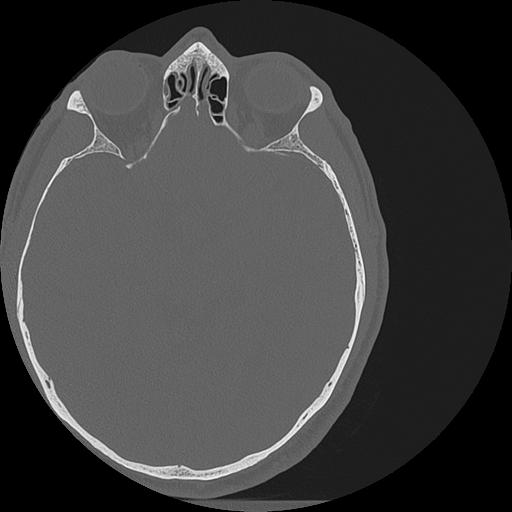

7 HUESO,,Vol,0.5,HUESO,,